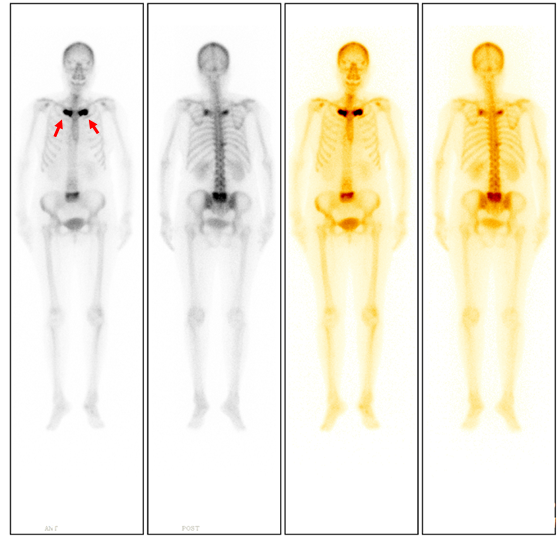

ECT全身骨顯像所見(圖1):

ECT檢查結(jié)論:雙側(cè)第1前肋、T10、右側(cè)第10肋椎關(guān)節(jié)、腰骶椎(L5為著)代謝異常增強,符合SAPHO綜合征影像學(xué)表現(xiàn)。

如果臨床上懷疑SAPHO綜合征,最需要做的檢查是ECT全身骨掃描。ECT可特征性表現(xiàn)為前上胸壁異常放射性濃聚灶,典型的圖像為“牛頭征”(圖1箭)。早期診斷、及時治療能夠避免患者并發(fā)癥的發(fā)生。同時,ECT能夠展示全身骨骼受累的情況,準確評估疾病范圍及疾病的活動程度。對于治療期間的患者,ECT隨訪可以評估患者對藥物治療的敏感性,并監(jiān)測疾病進展。(核醫(yī)學(xué)科)